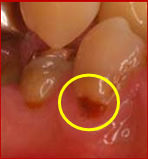

また、加齢と歯周病によって歯肉が下がり、歯根部が露出してしまうことがあります。

その場合、知覚過敏や根面う蝕を発症しやすくなりますので、注意が必要です。